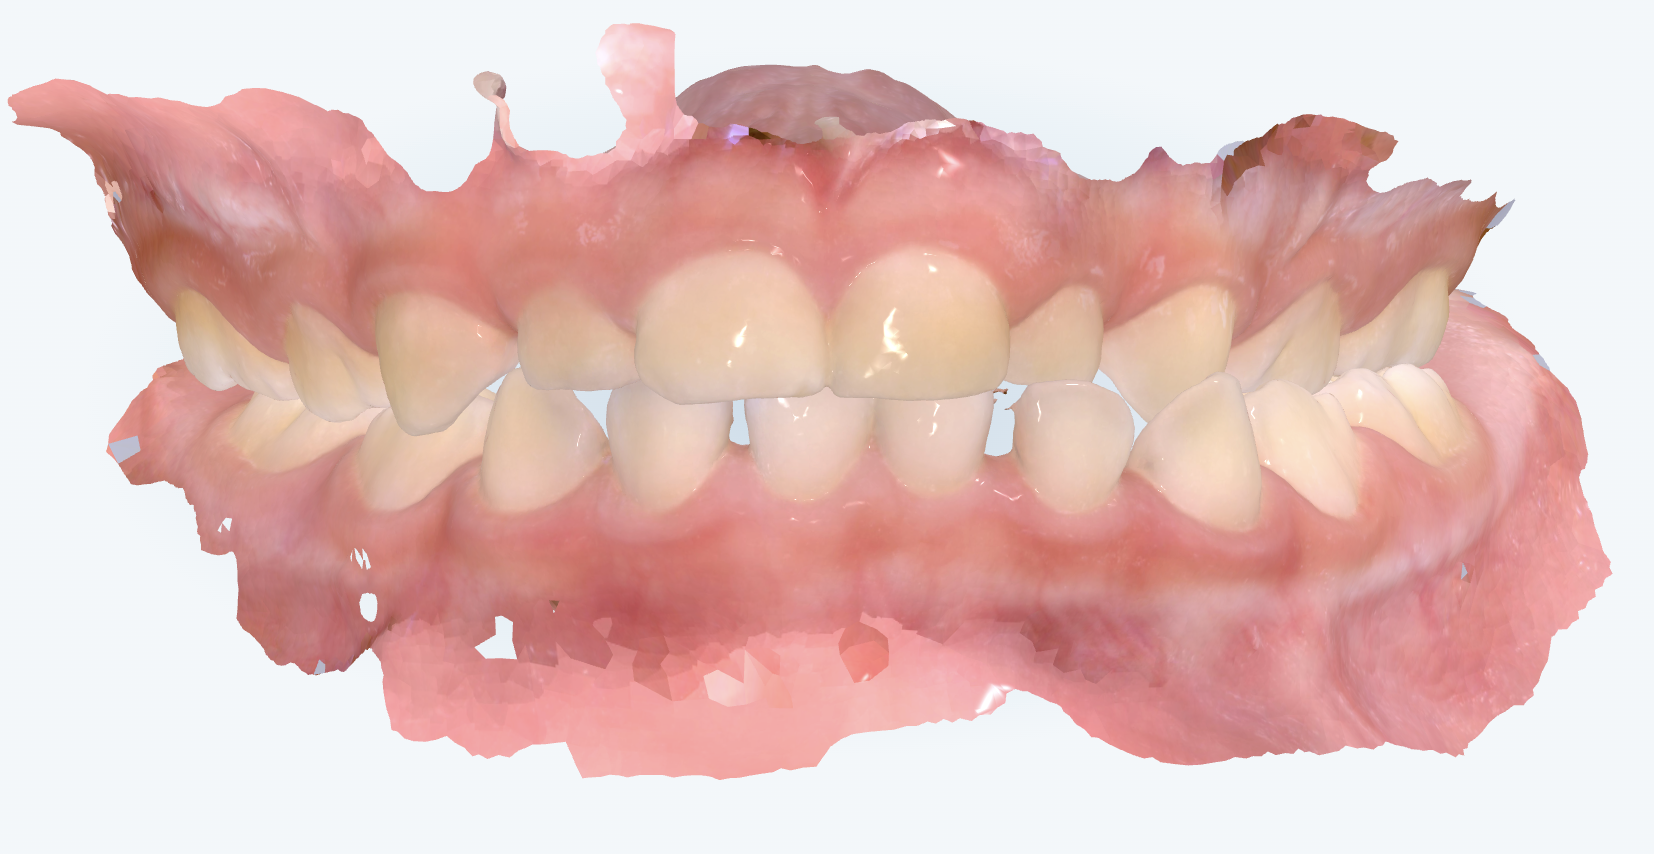

初診時の画像診断

左側の噛み合わせが上下反対に噛んでいました。下顎の左方向へのズレにより交叉咬合でした。

指吸いにより前歯は出っ歯傾向になっていました。